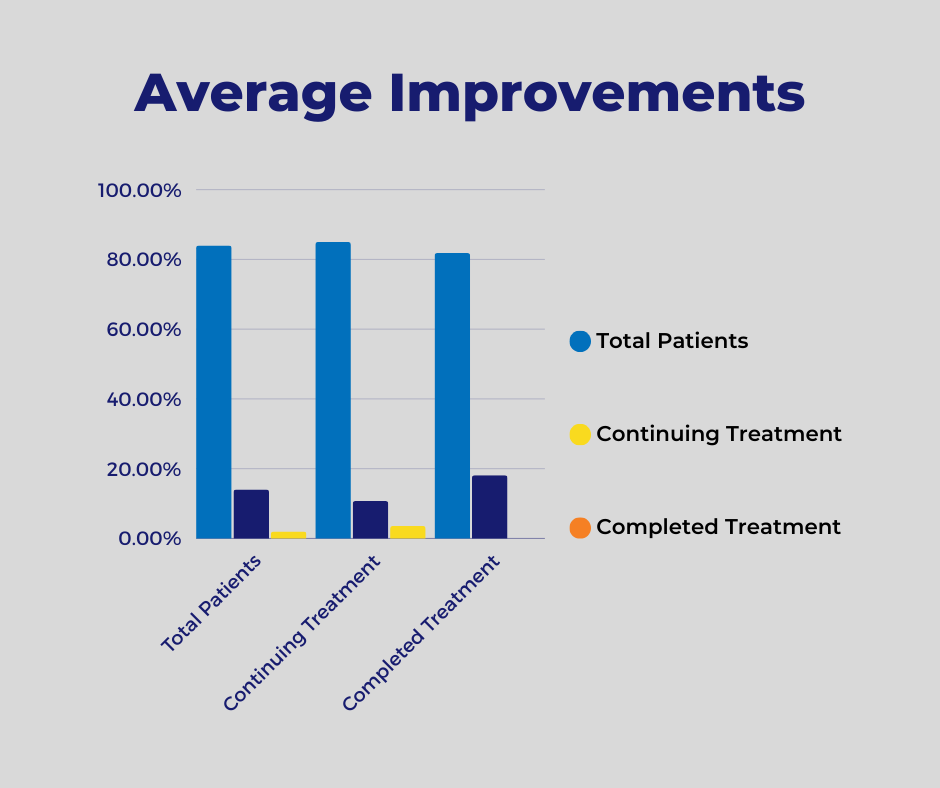

During the time reviewed, we found only 24 patients still receiving therapy at the final date for review. The individual average improvement for these patients at the end date was 60%. Of the 26 patients no longer participating in treatment, there was an individual average

Figure 3 Improvements Average Per Patient

improvement of 55% to their curvature. This change is congruent with our observations showing the largest change in curvature realized toward the end of therapy.

Figure 3 Improvements Average Per Patient